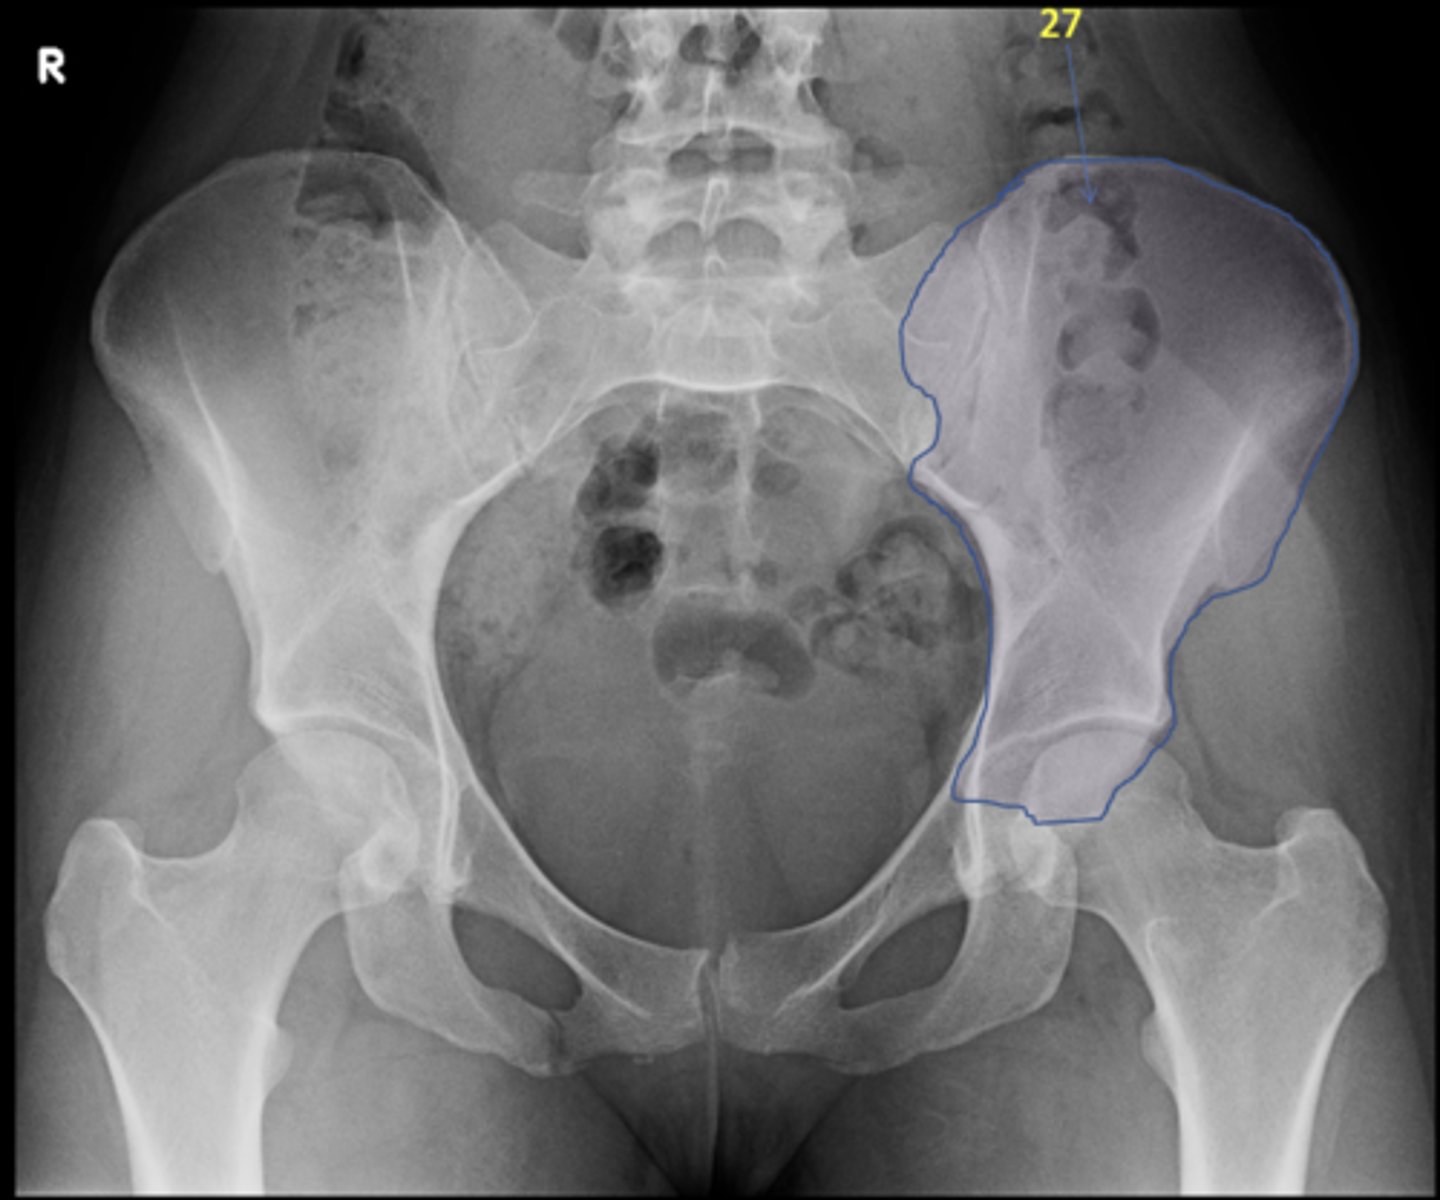

1

New cards

AP pelvis

View?

24

Left ilium

ID 27

26

Bladder

ID 29

27

Ascending colon

ID 30